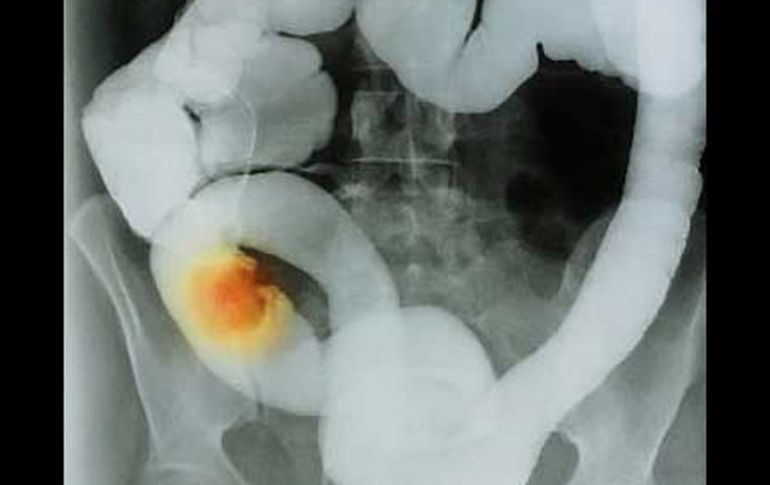

GUADALAJARA, JALISCO (06/AGO/2010).- Una investigación del Instituto Mexicano del Seguro Social (IMSS) concluye que la obesidad, junto con el consumo excesivo de carnes rojas y una vida sedentaria aumentan la posibilidad de desarrollar cáncer de colon.

La obesidad central, la que se concentra en el abdomen, es el principal factor de riesgo encontrado para el desarrollo de cáncer de colon, aseguraron los investigadores.

En el muestreo quedó de manifiesto que la ya referida obesidad central fue, con un 63.8 por ciento de presencia en las personas estudiadas, el factor de riesgo más importante como disparador del cáncer de colon.

Otro referente importante, fue el relativo a los cambios al evacuar, parámetro que se captó en 97 de los pacientes evaluados, equivalentes al 60.6 por ciento de la muestra.

En tanto que el sedentarismo también se ubicó como un elemento de riesgo para este tipo de cáncer. En este punto los investigadores dijeron que este parámetro se captó en el 60 por ciento de los pacientes estudiados.

Los médicos de la Unidad de Medicina Familiar (UMF) No. 171 del IMSS señalaron que un alto consumo de carnes rojas, reportado en el 31.9 por ciento del total de sujetos, fue también un hallazgo correlacionado al desarrollo de cáncer de colon.

Los investigadores explicaron que aunque en particular en este rastreo no se encontró con una frecuencia significativa la presencia de sangre en excremento -apenas en el 3.8 por ciento de los sujetos-, la determinación de una herramienta valiosa para diagnosticar esta afección en fases tempranas.

Se trata de un estudio barato que desde el primer nivel de atención, es decir, en las unidades de medicina familiar, se realiza y puede arrojar cierta luz en cuanto a la presencia de patologías intestinales, entre ellas, el cáncer de colon.